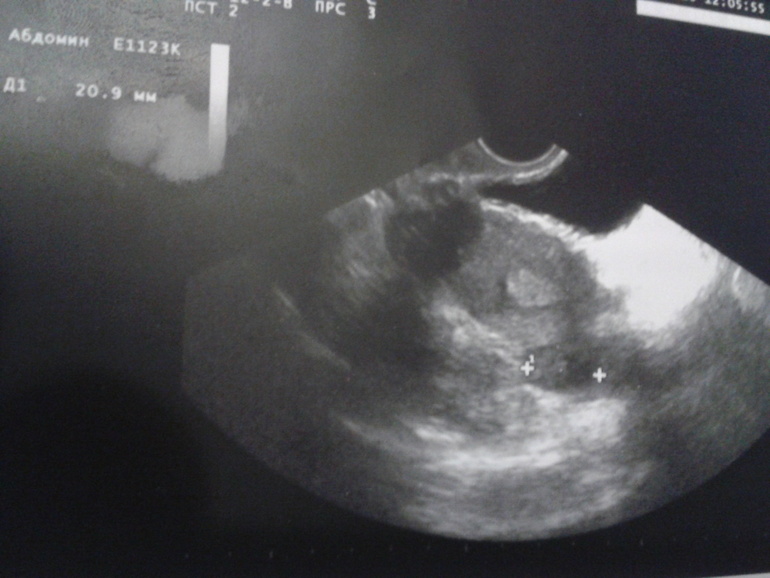

Писала пост без снимка,вот нашла его....что видно на снимке,есть ли желтое тело?

Скорее всего крестики это все же Я и ЖТ в нем черное пятно

К геникологу еще не попала,а узист сказала что есть постовуляторная жидкость в небольшом количестве,это говорит то О была 48 часов назад, а вот образовалось ли желтое тело и какого оно размера она не сказала и я забыла спросить

Вот и я так понимаю что оно должно быть,а узист ничего не сказала и в описании не указала его размеры

Вот в этом то и вопрос,узистка не написала ничего о желтом теле....